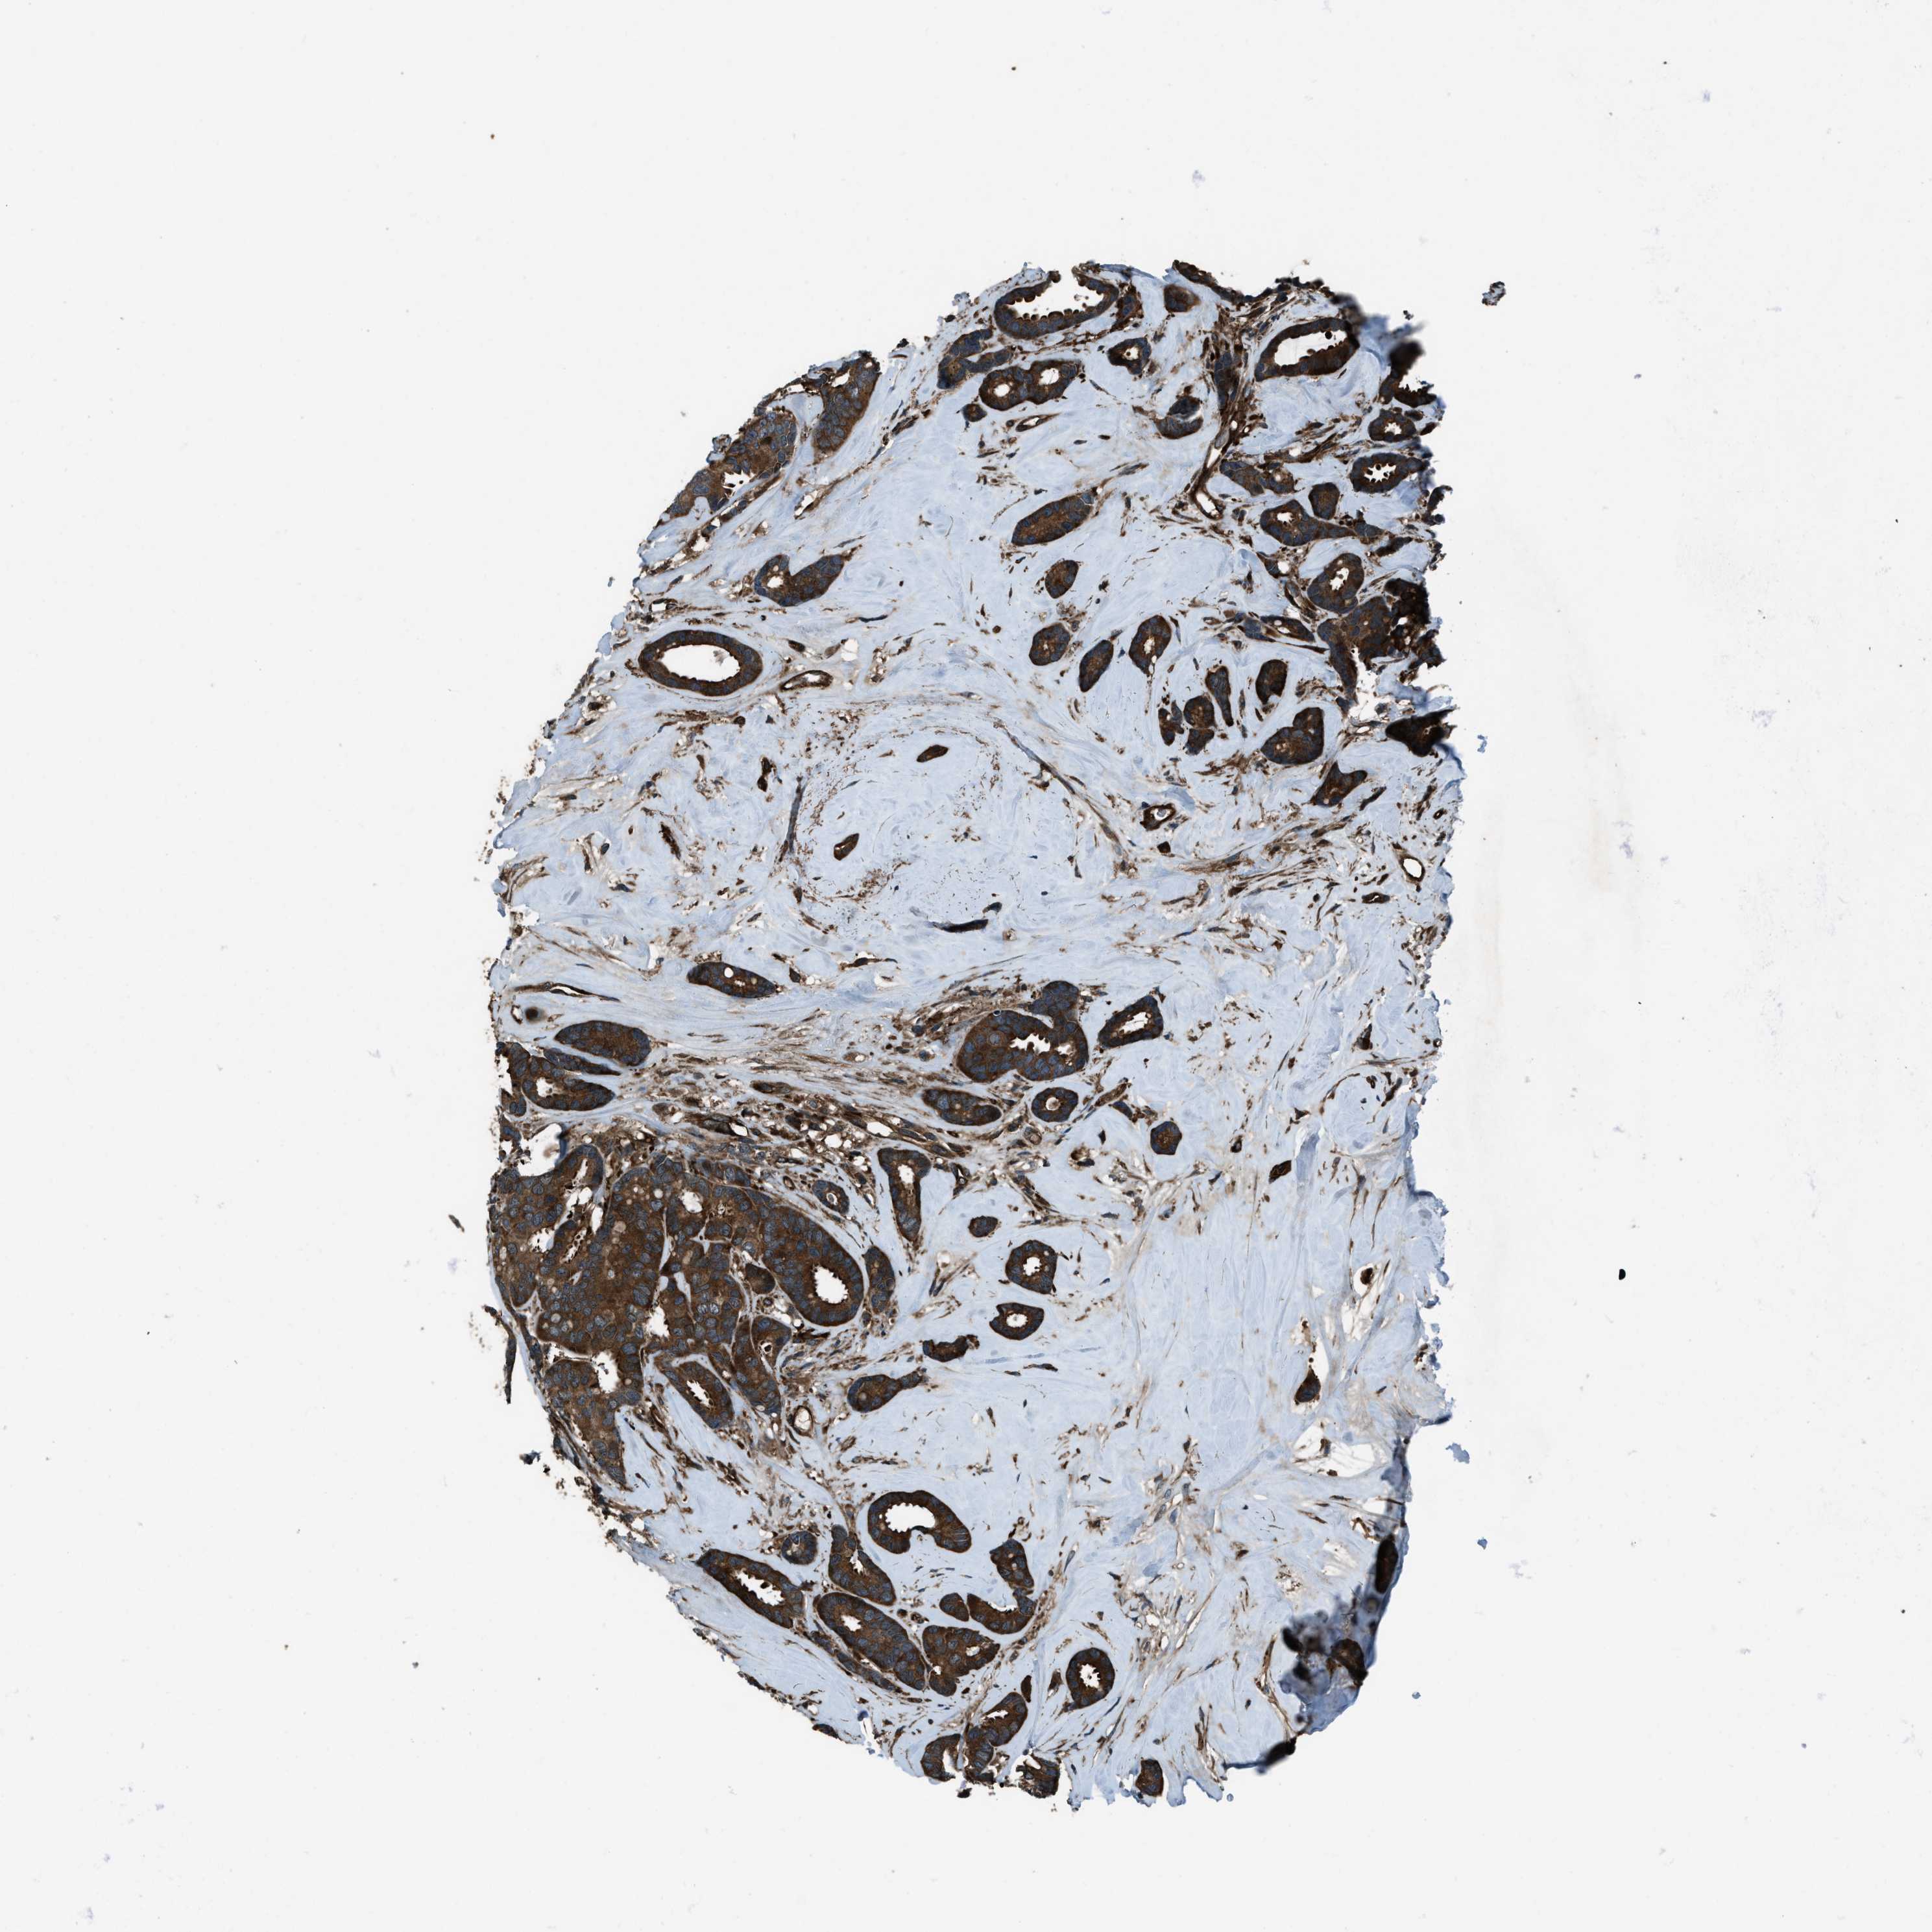

CANCER BREAST CANCER Show tissue menu

BRCA TCGA BRCA VALIDATION PROTEIN EXPRESSION